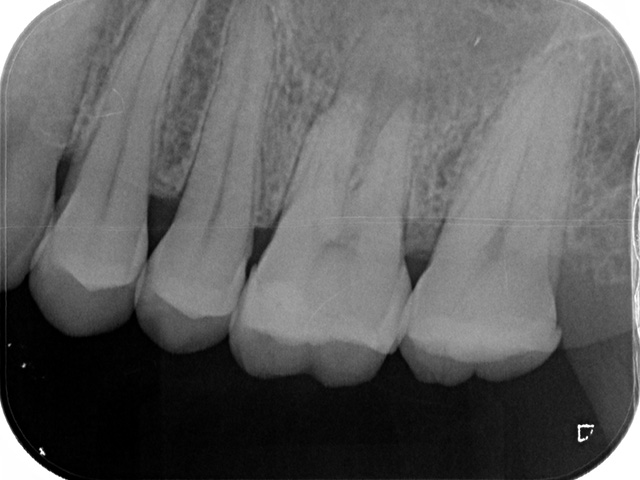

| 検査・診断 | X線(2次元)による診断 | 歯科用CT(3次元)を用いた精密な診断が可能 |

| デンタルレントゲン | CT画像 |